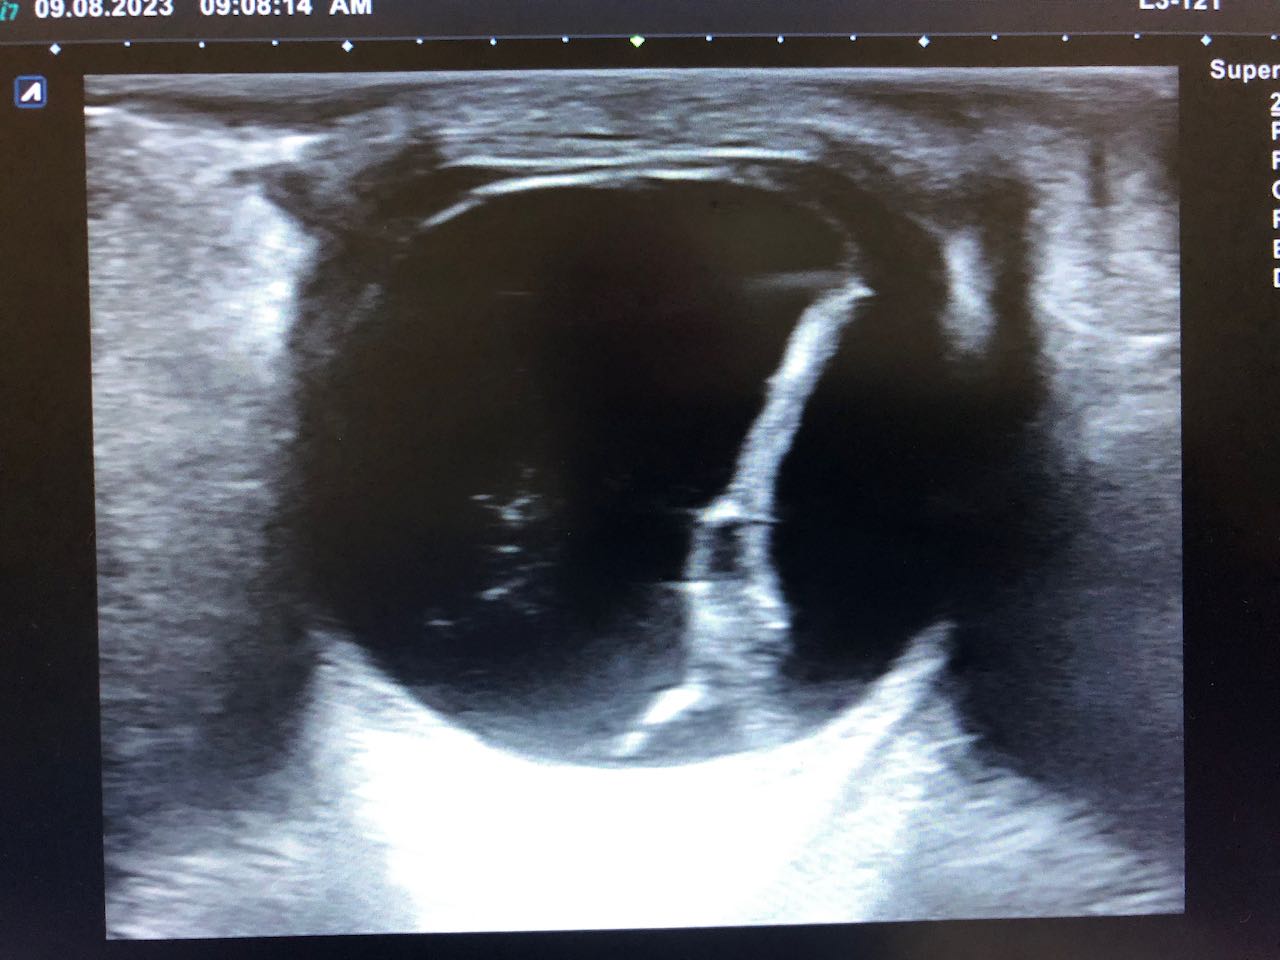

Citado en cita forzada, refiere molestias oculares, con sensibilidad a la luz, que le obliga a mantener el ojo cerrado, acude por precisar gotas para la conjuntivitis, ante la dificultad idiomática y considerar que el paciente es poco preciso en la descripción de los síntomas, pues ante la pregunta de «si tiene dificultades en la visión» el paciente se reitera que le molesta muy cierra el ojo, y en relación con el dolor que es como si tuviera algo que le roza. Se procede a la exploración ocular, observando un ojo derecho normal con blefaroespasmo en ojo izquierdo (OI), hiperemia ocular tarsal, con pupilas reactivas, fluortest negativo y presión intra ocular (medición palpebral), normal en los dos ojos. Ante la incongruencia de la sintomatología referida y los hallazgos exploratorios, se considera indicado hacer una ecografía ocular, en la que se apreció signos de desprendimiento de retina y coroides del OI.

Se confirma desde Oftalmología el diagnóstico: Desprendimiento de retina casi completo junto a desprendimiento de Coroides temporal en OI de contenido hiperecogénico, no se aprecian masas.